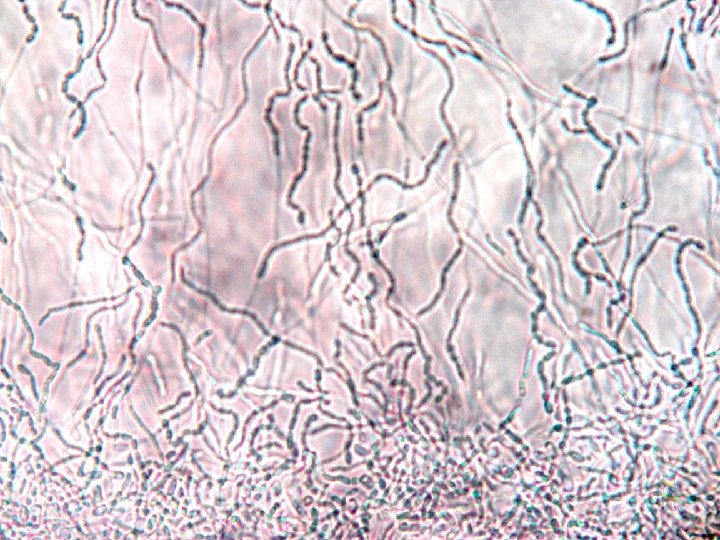

Candida krusei Micromorfologia Blastoconídios são ovais, cilíndricos, dispostos verticiladamente na constrição da pseudohifa. Lembram “palitos de fósforo amontoados”. Pseudohifas Alongadas, delgadas e ramificam lembrando “ galhos de árvores”